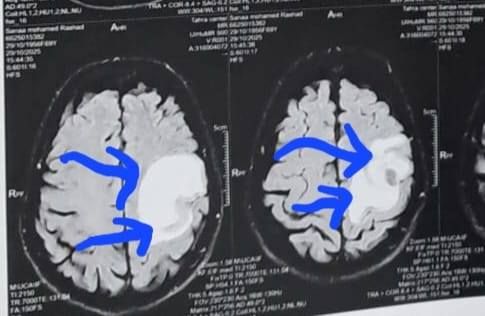

وكشف الدكتور إبراهيم الغريب رئيس قسم جراحة المخ والأعصاب بالمستشفى، أنه تعود تفاصيل الحالة إلى استقبال المستشفى المريضة بالعيادة الخارجية وهي تشكو من تنميل وضعف بالجانب الأيمن وثقل بسيط في الكلام، وبإجراء الفحوصات اللازمة من أشعة مقطعية ورنين مغناطيسي بالصبغة، تبين وجود ورم بالمخ، وتم إعطاؤها العلاج المناسب لحين استكمال الفحوصات.

أشعة المريضة

الأشعة الخاصة بالمريضة

الأشعة